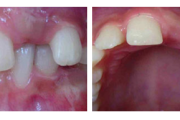

Koonilise kujuga lisahammas ülemiste tsentraalsete lõikehammaste vahel.

Suulaepoolt lõikunud koonilise kujuga lisahammas